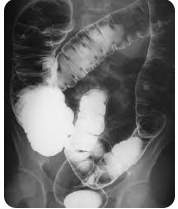

Figura 2: Série de posições no enema opaco. Fonte: Radiopaedia

5. Posições Radiográficas e Documentação

Posições Obrigatórias

| Posição | Objetivo |

|---|---|

| AP Abdome | Visualização geral do cólon |

| PA com compressão | Detalhamento da mucosa (duplo contraste) |

| RAO (R. Anterior Oblíqua) | Visualização do cólon ascendente |

| LAO (L. Anterior Oblíqua) | Visualização do cólon descendente |

| Perfil (lateral do reto) | Avaliação de reto e ânus |